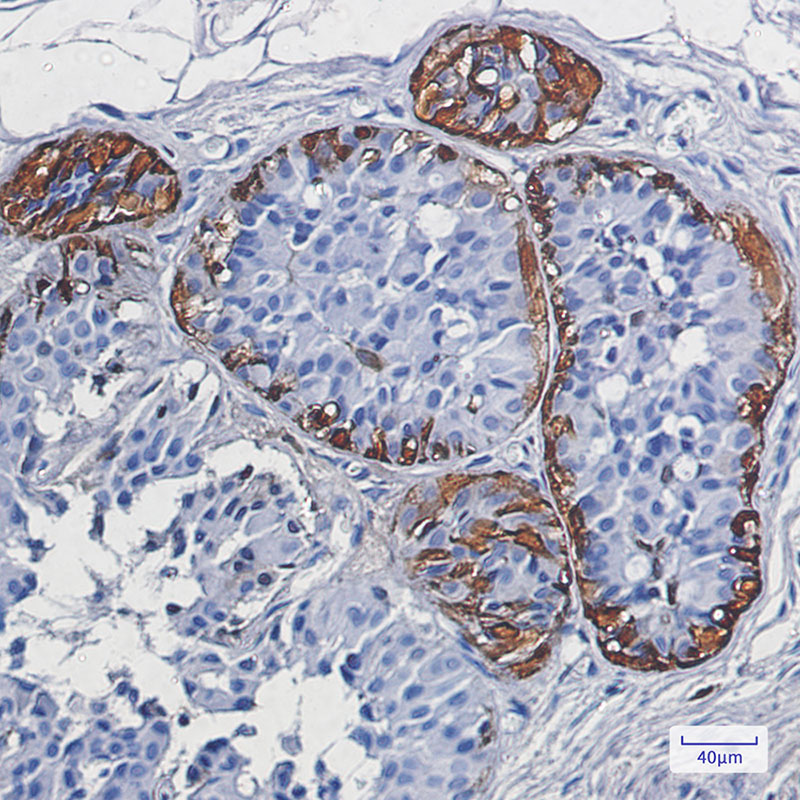

S100 beta Rabbit mAb

| WB, IHC-P |

| Dilution | WB~~1:1000-1:5000 IHC-P~~1:50~200 |

S100B is a member of the S100 family of proteins containing 2 EF-hand calcium-binding motifs. S100 proteins are localized in the cytoplasm and/or nucleus of a wide range of cells and are involved in the regulation of a number of cellular processes such as cell cycle progression and differentiation. S100B may function in neurite extension, proliferation of melanoma cells, stimulation of Ca2+ fluxes, inhibition of PKC-mediated phosphorylation, astrocytosis and axonal proliferation, and inhibition of microtubule assembly. Chromosomal rearrangements and altered expression of this gene have been implicated in several diseases, including Alzheimer's disease, Down's syndrome, epilepsy, amyotrophic lateral sclerosis, melanoma, and type I diabetes.